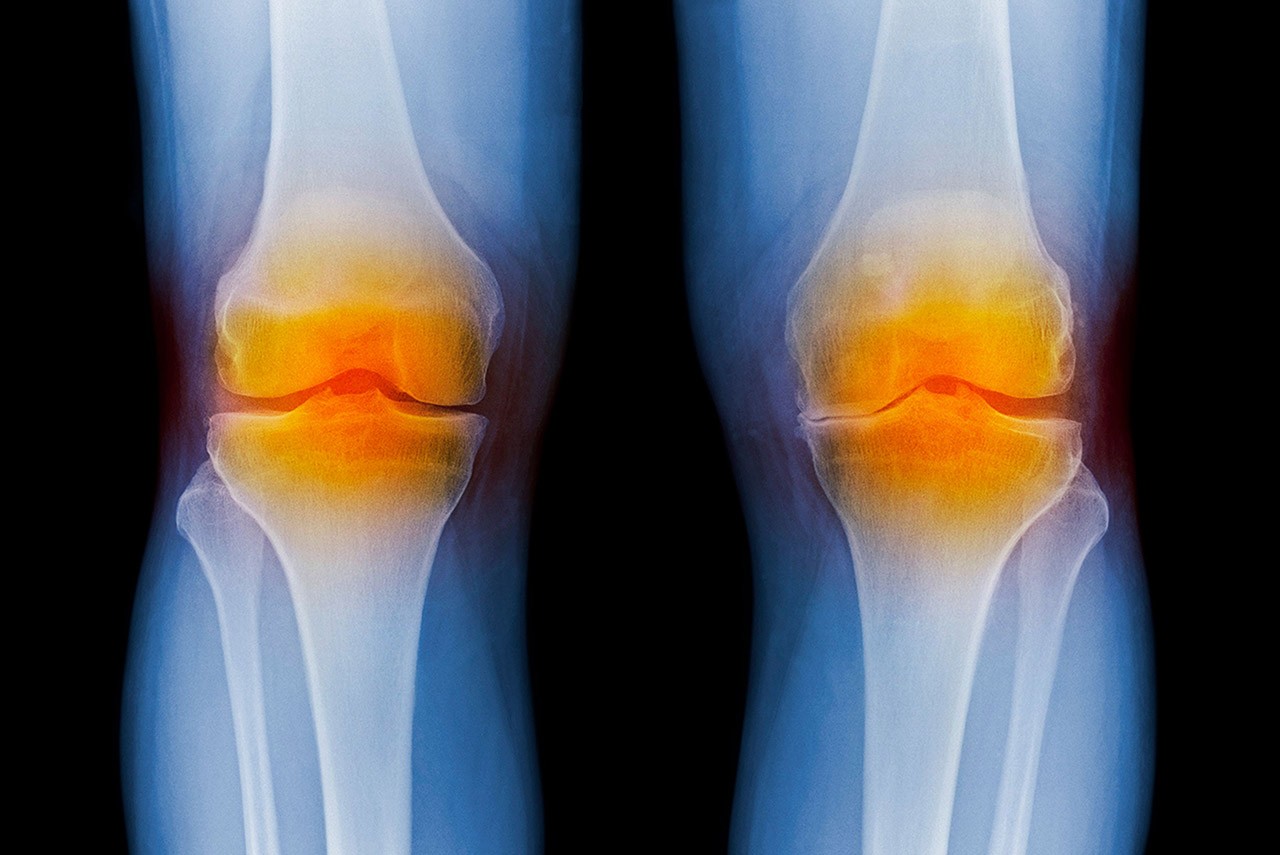

Dean Marcolongo and the team developed biomimetic proteoglycans, or BPGs—lab-engineered molecules that can withstand the inflammatory enzyme attacks that typically cause joints to break down. When these BPGs are injected into joints, the researchers found they can molecularly engineer damaged cartilage, repairing degenerated tissues.

It’s a new strategy for patients with osteoarthritis, a degenerative disease of the joints for which there is no cure. Today, if a patient has early arthritis symptoms in their joints, they have limited options—take ibuprofen, get a steroid injection, undergo physical therapy or wait until later in life to get a total replacement.

“We don’t have many treatments to treat early arthritis and stop the progression to painful and debilitating symptoms,” says Dean Marcolongo. The treatment she helped develop has potential to fill that gap. It’s minimally invasive, requiring just a simple knee injection.